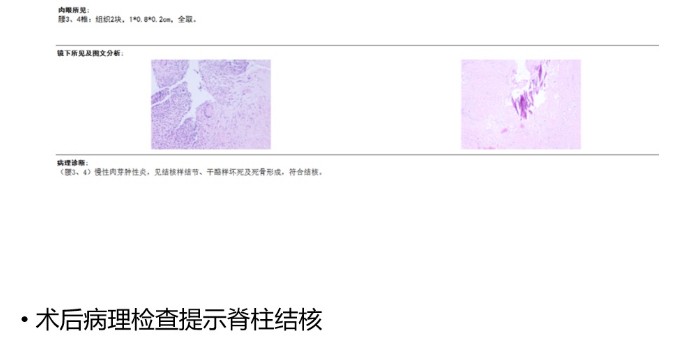

為解決老人病痛���,脊柱外科錢軍博士團(tuán)隊(duì)對(duì)其進(jìn)行了詳細(xì)的查體以及全面細(xì)致的評(píng)估�����,診斷為L3�����、4脊柱結(jié)核伴病理性骨折���、椎旁膿腫����,患者腰部疼痛癥狀逐漸加重�,病灶已經(jīng)壓迫神經(jīng)引起了截癱�。

經(jīng)過積極充分的準(zhǔn)備,錢軍博士團(tuán)隊(duì)為患者成功實(shí)施了L3���、L4脊柱結(jié)核病灶清除植骨融合內(nèi)固定術(shù)��,手術(shù)順利�,術(shù)后患者腰腿痛癥狀明顯緩解����,患者及家屬對(duì)治療效果非常滿意,對(duì)醫(yī)院的醫(yī)療技術(shù)以及優(yōu)質(zhì)的服務(wù)護(hù)理稱贊不已����。